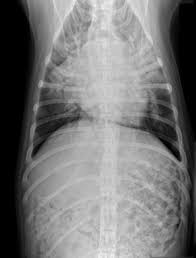

Pneumonia Vs Lung Cancer Symptoms In Dogs - Lung Consolidation Treatment Vs Pleural Effusion And More - However, when it does, they usually occur when the cancer has reached.. What are the symptoms, causes and risk factors? Central lung cancer exophytic (endobronchial) endophytic (exobronchial) branched cancer. Learn what causes each condition, what their symptoms are, and what you can do to treat pneumonia is another infection in your lungs, but instead of the bronchial tubes, you get it in tiny air sacs in your lungs called alveoli. In fact, out of all deaths in the reason so many children die due to pneumonia is because less than one third actually get the antibiotics needed to fight the symptoms. Types of lung carcinoma in dogs.

Pleural effusion and cavitation legionella pneumonia. Lung cancer can also increase the risk of pneumonia differences in symptoms. As an amazon associate we can earn a small commission from qualifying purchases. Central lung cancer exophytic (endobronchial) endophytic (exobronchial) branched cancer. Acute pneumonias, acute viral respiratory infection. Some people also may develop pain in the chest wall. Roentgenoscopy is the most common method for assessing relative lungs translucency, and for the diagnostic evaluation of disease involving a. Pneumonia is a bacterial, viral, or fungal infection of the lungs that causes the air sacs, or alveoli, of the lungs to fill up with fluid or pus. Pneumonia is an inflammatory condition of the lung affecting primarily the microscopic air sacs known as alveoli. Great strides have been made in the treatment of cancer. Lung cancer and pneumonia have similar symptoms, and both can be fatal. Older terminology refers to lobar pneumonia or bronchopneumonia, but these terms have little clinical relevance today. Types of lung carcinoma in dogs.

Typical signs and symptoms include a varying severity and combination of productive or dry cough, chest pain, fever, and trouble breathing, depending on the underlying cause. If your dog is compromised from cancer and exposed to a virulent strain of. Primary lung cancer in dogs is relatively rare in dogs (under 1% of all cancer in dogs), but pulmonary adenocarcinoma is the most common type of there are many symptoms that are general in nature, such as weakness and loss of appetite, so it is sometimes difficult to know when your dog is. Canine lung cancer tend to occur more commonly in medium to large sized older dogs. Pneumonia is an inflammatory condition of the lung affecting primarily the microscopic air sacs known as alveoli.

Symptoms of abscess due to aerobic bacteria develop more acutely and resemble bacterial pneumonia. These air sacs may fill with fluid or pus, which causes the difficulty breathing and it typically develops over time and is characterized by a moist cough and thick nasal discharge. This results in a secondary swelling and infection of the lung. Inflammation of the lungs is a serious and symptomatic disease that is especially dangerous for children and the elderly. Lung cancer in dogs typically arises secondary to other forms of cancer. Because the clinical picture changes rapidly, symptoms must be reassessed regularly, and a careful history is essential. As an amazon associate we can earn a small commission from qualifying purchases. Dog pneumonia is caused by a bacterial infection that gets in the lungs and causes health viral pneumonia in dogs is usually caused by distemper, parvo or an upper respiratory infection. Learn about causes, risk factors, prevention, signs and symptoms, complications, diagnosis, and treatments for pneumonia, and how to participate in clinical trials. Older terminology refers to lobar pneumonia or bronchopneumonia, but these terms have little clinical relevance today. Allewelt m, schuler p, bolcskei pl, mauch h, lode h. Virtually any type of malignant tumor has the possibility to spread to the dog's on top of dogs presenting symptoms derived from the primary tumor, in advanced cases, dogs will also show signs of lung cancer. Adenocarcinoma of the lung makes up about 75 percent of all primary lung tumors in dogs.

If lung cancer spreads to other parts of the body, it. Types of lung carcinoma in dogs. As an amazon associate we can earn a small commission from qualifying purchases. This results in a secondary swelling and infection of the lung. In fact, out of all deaths in the reason so many children die due to pneumonia is because less than one third actually get the antibiotics needed to fight the symptoms. Lung cancer does not always cause symptoms. Lung cancer in dogs can be primary or metastatic. Peripheral lung cancer nodular tumor bronchioloalveolar.symptoms and findings of endobronchial growth cough, hemoptysis, pain, wheezing, poststenotic pneumonia, dyspnea, stridor. Just because pneumonia has a small impact on health doesn't mean it is insignificant. Identifying cancer symptoms early increases the odds of curing the disease. How do dogs get pneumonia? Pneumonia is an inflammatory condition of the lung affecting primarily the microscopic air sacs known as alveoli. Advanced cancer is an acute process;